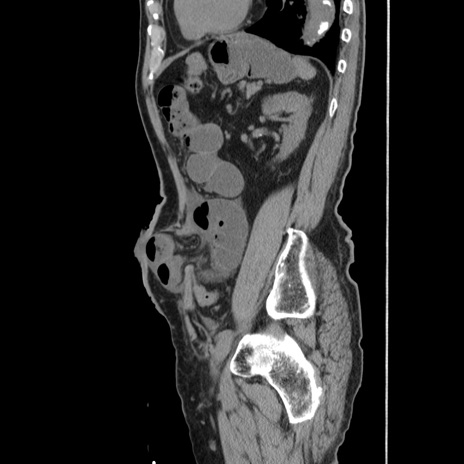

症例24(矢状断像)

【症例】80歳代男性

【主訴】左側腹部痛、嘔吐

【現病歴】本日早朝より左腹部に痛みあり。昼頃嘔吐認めたため、救急要請。

【既往歴】直腸癌(Mile手術)、胆摘

【身体所見】意識清明、BT 35.9℃、BP 221/93mmHg、SpO2 97%(RA) 、腹部:左ストーマ周囲に限局性の腹部膨隆あり。 膨隆部自発痛・圧痛あり・軟。

【データ】WBC 7700、CRP 0.09